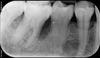

Sur le cliché panoramique initial de cette patiente de 38 ans, une perte osseuse localisée est visible au niveau de la première molaire inférieure droite.

Sur le cliché rétroalvéolaire (plus précis), l’atteinte osseuse présente une forme de « poche parodontale » typique. Le terrain familial est typique également puisque la mère de la patiente présente également une maladie parodontale.

Le traitement médical avec approche microbiologique de 6 séances sur 8 mois a permis de générer une cicatrisation osseuse. Les résultats visibles sur le cliché ont été obtenus en l’absence de toute chirurgie.